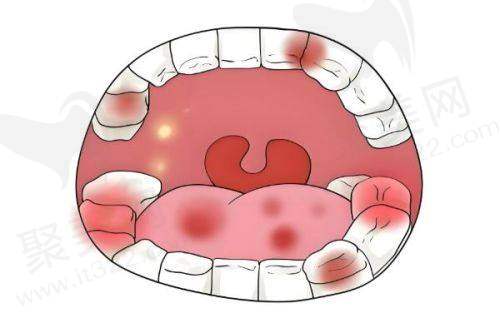

3. 诊疗服务:秦淮分院的营业时间也是09:00 - 18:00,全年无休。虽然分院面积不是特别大,但设备一点也不含糊,医生团队经验也特别丰富。特别是在儿童牙科和牙齿美容修复方面,有自己独特的特色。在儿童牙科领域,医院通过卡通主题诊室、互动游戏等方式,能有效缓解儿童就诊时的焦虑情绪。